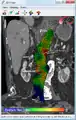

Biomechanical AAA rupture risk prediction